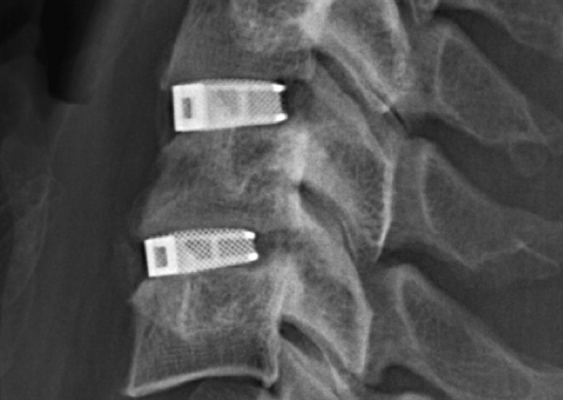

Рентгенограмма при искусственном поясничном межпозвонковом диске

Доступ к межпозвонковому диску и телам смежных позвонков, проводится из переднего поясничного доступа. Затем очищается торцовая поверхность тел позвонков с целью их подготовки к имплантации искусственного протеза.

Поврежденный диск удаляется (дискэктомия) и при помощи специальных высокоточных инструментов в межтеловый промежуток вставляется диск поясничного отдела позвоночника M6-L. После успешной установки диска M6-L разрез зашивается.

В M6-L существуют две внешние титановые пластины с килями для фиксации диска в костной ткани тела позвонка, которые покрыты плазменным титановым напылением, стимулирующим прорастание кости в металлические пластины, что в свою очередь обеспечивает длительную фиксацию и стабильность диска в кости.

После операции хирург тщательно проверяет положение эндопротеза. Кроме того, для определения состояния эндопротеза проводится рентген.